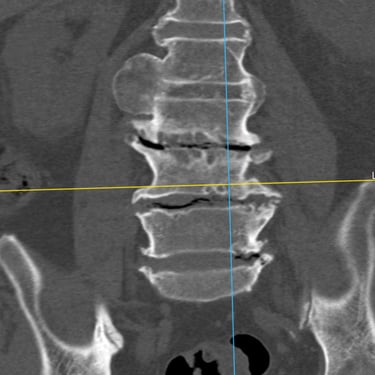

🧠 Fractura Vertebral Lumbar: Estabilización Segura con Fijación Transpedicular (FTP).

La fractura vertebral lumbar genera inestabilidad y dolor severo. La artrodesis con fijación transpedicular es una técnica quirúrgica eficaz que estabiliza la columna, previene desplazamientos vertebrales y mejora la recuperación funcional del paciente.